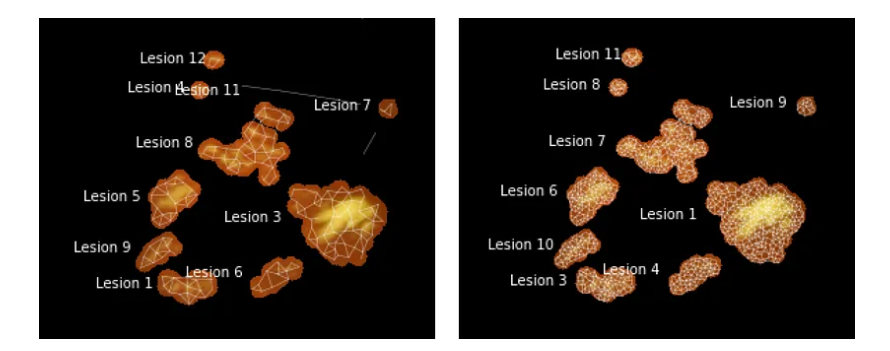

终端神经元数量越多,形状近似越准确,但运行时间也越长(左:200 个神经元,右:1,000 个神经元)。

使用 GNG 计算聚类簇时,一些设置至关重要。特别是,值得从大量初始神经元开始。在第 1 部分中提到的图像矢量量化示例中,我们从两个神经元开始。这样做的结果是一个图,该图在大多数时间将保持完全连接(回想一下,对于 GNG 来说,生成新神经元比删除现有神经元要容易得多)。这是一个问题,因为我们依靠计算断开连接的子图来确定不同病变的数量。最简单的解决方案是创建大量初始神经元(几千个,即比预期的不同簇数量多 2-3 个数量级)。虽然延长了训练时间,但一段时间后确实会导致分割越来越准确——最重要的是,与初始神经元数量较少的分割不同,它们不太可能具有需要多次迭代才能分离的连接段。

在大量迭代中使用相同的设置可以更好地分离近距离神经元